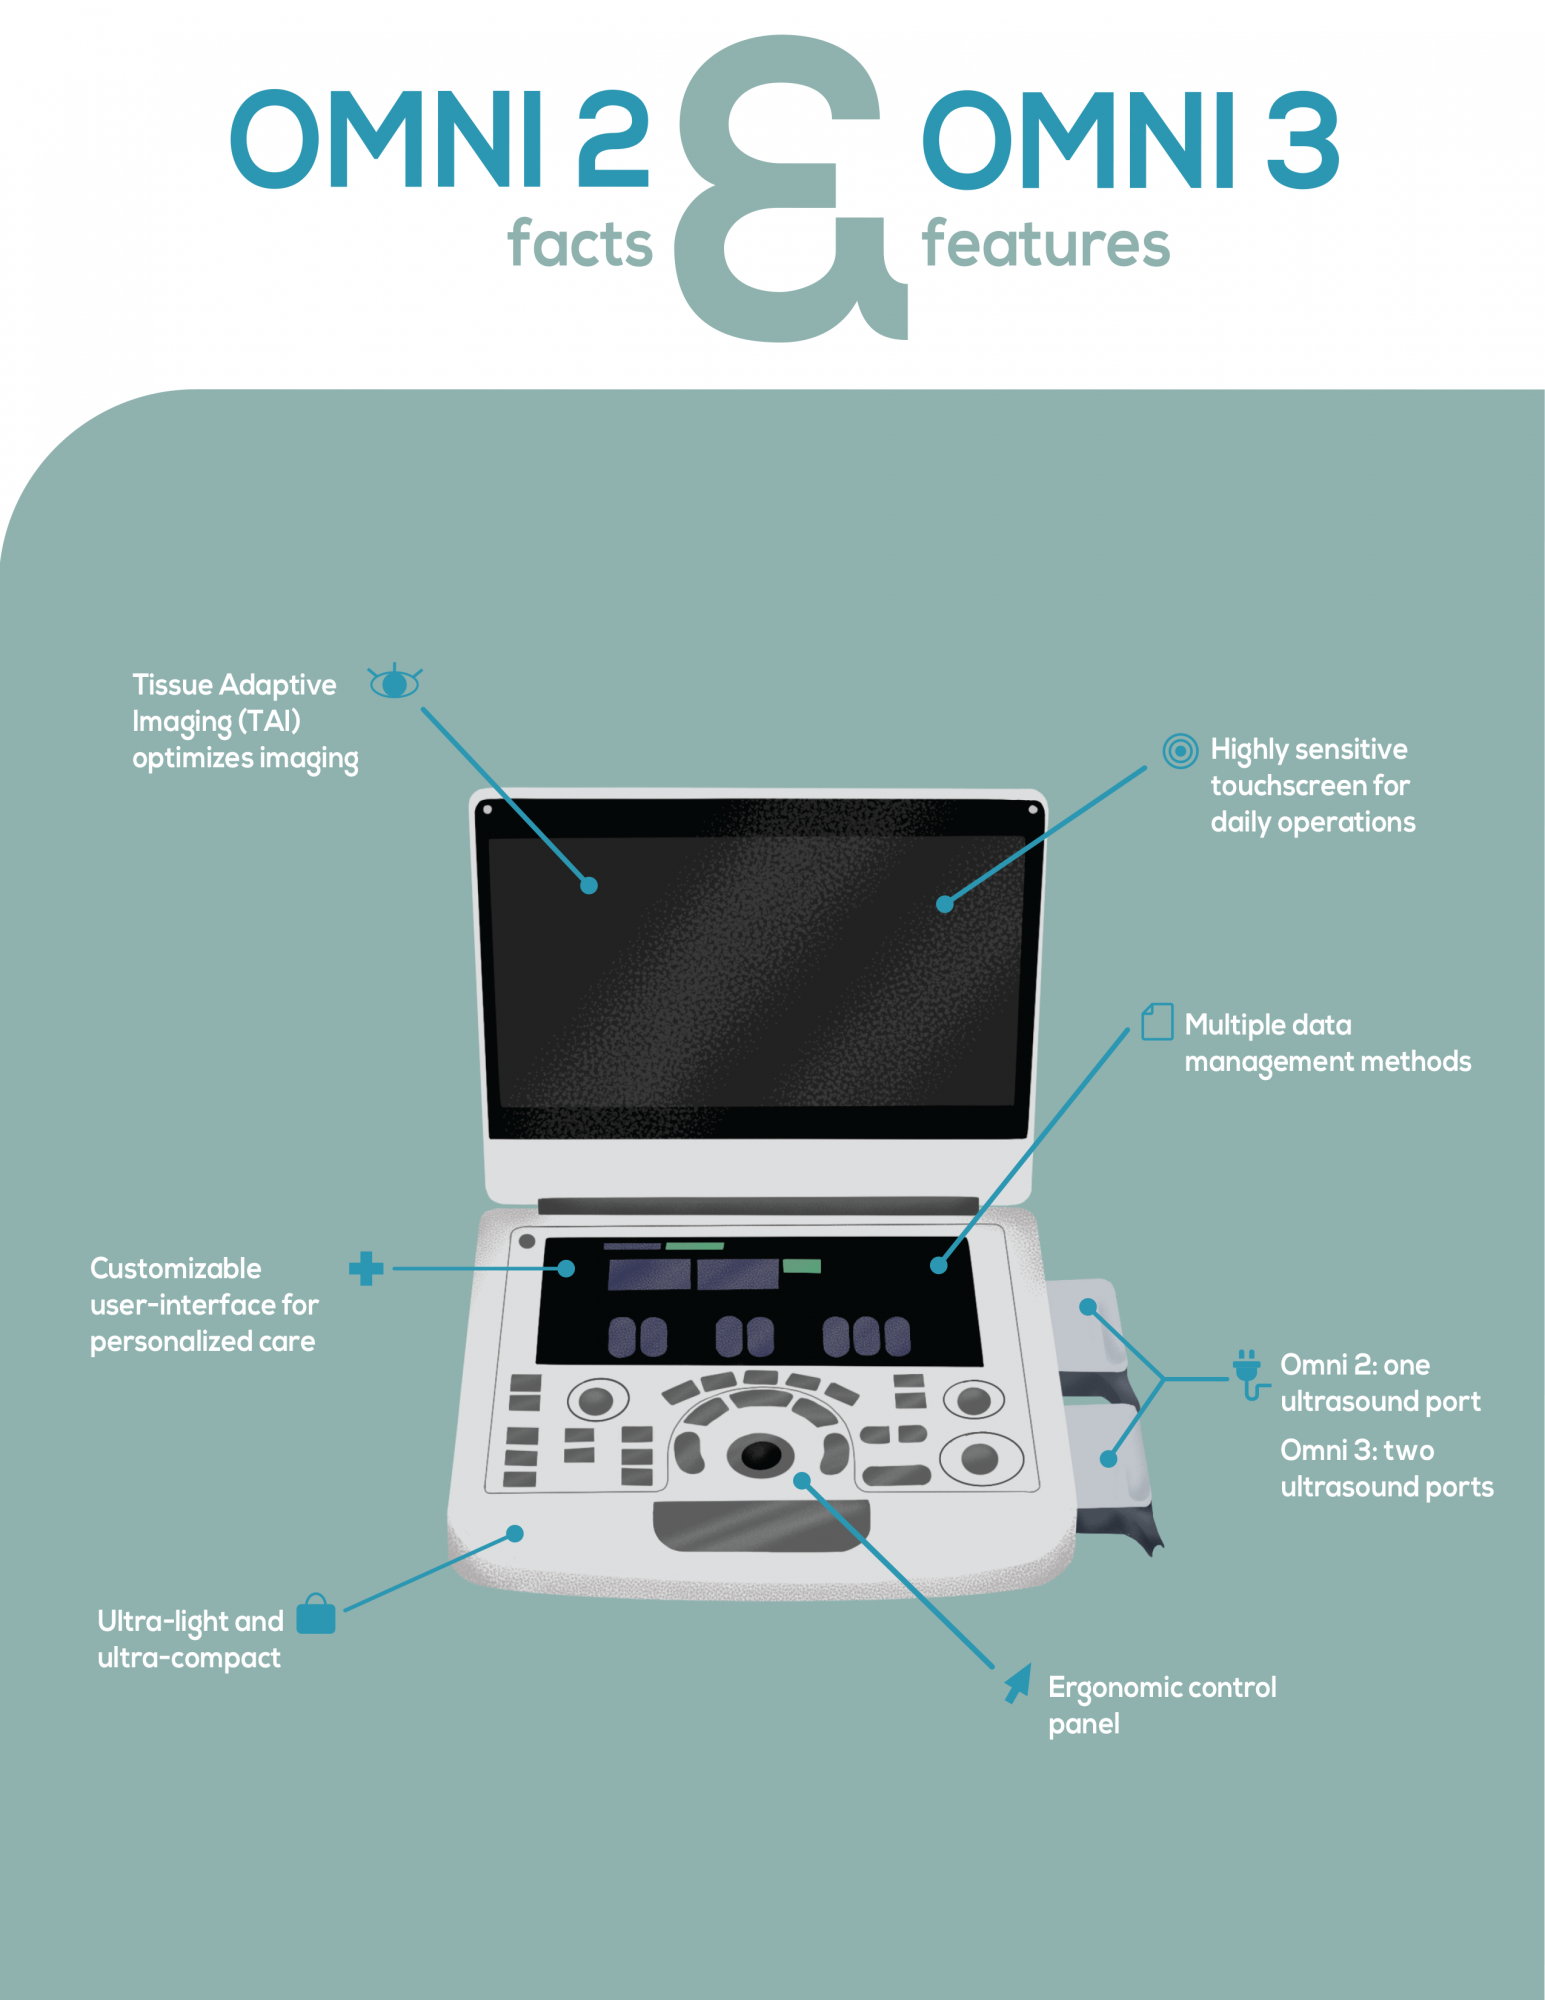

Revolutionary platform results in superb detail resolution, particularly at depth.

Tissue Adaptive Imaging (TAI) continuously and automatically optimizes imaging

allowing more focus on different kinds of animals.

Dual transducers design can simplify workflow and improve the diagnostic efficiency

Ergonomic control panel with high sensitive touch screen ensures everything at fingertips

Ultra-light and ultra-compact design facilitates maneuverability and portability

High sensitive touch screen for daily operation

Dedicated presets and measurement packages for veterinary applications

Customizable user interface for personalized design

Multiple data management methods: DICOM, network, PDF, AVI and BMP file export